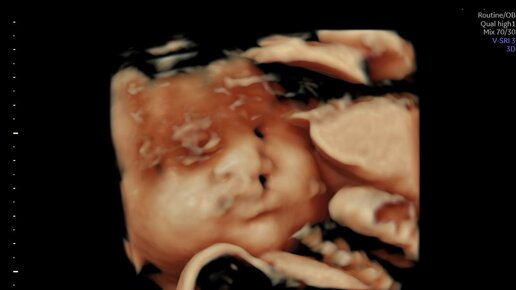

Заячья губа, волчья пасть. Часть первая. Как мы узнали о нашем диагнозе

Заячья губа, волчья пасть. Часть вторая. Беременность после диагноза . Роды.

Всем доброго времени суток! Меня зовут Алена, я мама счастливого ребенка с расщелиной губы и неба. Сын родился в США в мае 2024. На момент написания статьи нам всего два с половиной месяца. Мою историю с самого начала можно прочитать тут 👉: Часть вторая. Итак в январе после подробного узи мы с мужем нашли таки группу поддержки в англоязычной соц сети с названием F**ebоок. И даже не одну! Кому интересно ищите по поиску cleft lip cleft palate support . Перечитали кучу информации на обоих языках. И убеждали себя что у нас то как раз самый легких случай! И даже небо (palate) будет не затронуто...